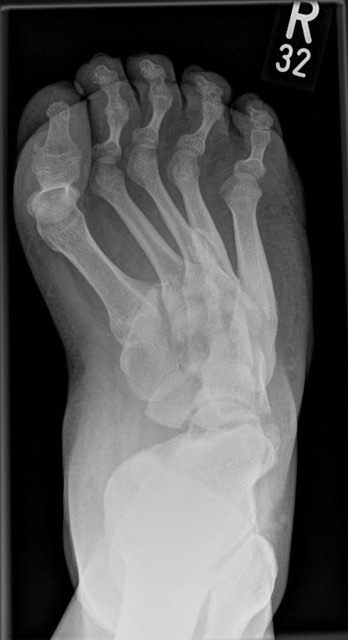

• Fuß belastet dp und seitlich (Abb. 14 und 15)

Typische Merkmale der Standard-dp-Röntgenaufnahme des Fußes im Stand

• Talus und Calcaneus verlaufen fast parallel

• Os naviculare ist gegenüber dem Talus nach medial gedrängt

• Metatarsalia überlappen sich basisnah

• Metatarsale I erscheint verkürzt

• Metatarsus adductus